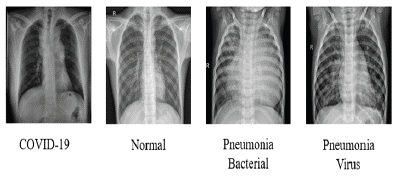

• To present new models for detecting COVID-19 and other pneumonia cases using chest X-ray images and CNNs. The proposed models were developed to provide accurate diagnostics in more output classes than previous studies, covering two scenarios: binary classification (COVID-19 vs. Non-COVID) and 4-classes classification (COVID-19 vs. Normal vs. Bacterial Pneumonia vs. Viral Pneumonia). Figure 1 illustrates samples of images used for this study.

Samples of the involved categories.

Figure 1: Samples of the involved categories.

Source: Authors